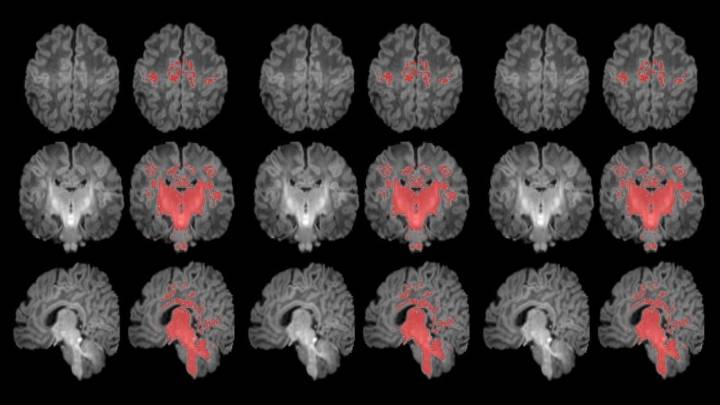

Un estudio mide con resonancia magnética la mielinización cerebral de los recién nacidos ISGlobal

Un estudio pionero publicado en la revista Environment International concluye que la exposición a la contaminación atmosférica durante el embarazo se asocia con una maduración cerebral más lenta en los recién nacidos . Este trabajo, fruto de la colaboración entre el Hospital del Mar, el Instituto de Salud Global de Barcelona (ISGlobal) y el CIBERESP, es el primero en analizar el desarrollo cerebral en el primer mes de vida.

La clave del hallazgo se centra en la mielinización, un proceso crucial en el que la mielina -una especie